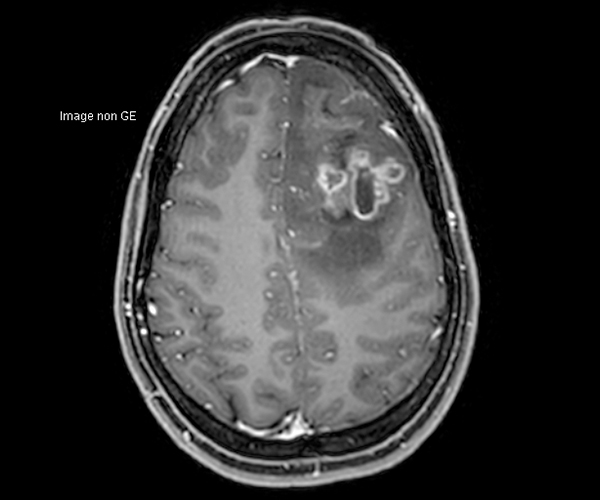

Concernant l’imagerie cérébrale, l’IRM 3T permet d’augmenter la sensibilité de détection de lésions ischémiques aiguës de petite taille, notamment chez les patients adressés pour accident ischémique transitoire (accident vasculaire cérébral), grâce à la séquence de diffusion dont le signal et la résolution sont augmentés.

L’amélioration de la résolution spatiale s’applique à l’exploration morphologique des hippocampes dans le diagnostic de la maladie d’Alzheimer, à la détection de petites lésions de sclérose en plaques ou de métastases, à l’étude fine du cortex dans les épilepsies.

L’augmentation de l’effet de susceptibilité magnétique à plus haut champ permet d’améliorer la détection des hémorragies et est utilisé également dans l’imagerie de perfusion (tumeurs) et l’IRM fonctionnelle (BOLD). L’allongement du T1 à plus haut champ entraîne une meilleure saturation des tissus statiques et par conséquent une augmentation du contraste sang/tissus dans l’AngioIRM.